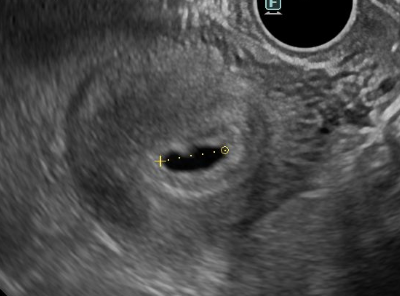

子宮内に、黒い袋が見え始めます。これが、胎嚢と呼ばれる妊娠初期に子宮の中で赤ちゃんを包む袋です。